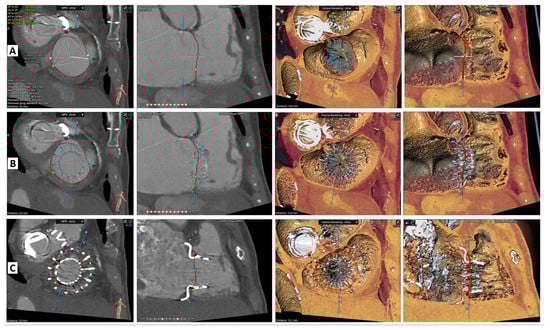

2. Cardiovalve Cases

4.2. Cardiovalve

- Barreiro-Perez, M.; Estevez-Loureiro, R.; Baz, J.A.; Piñón, M.A.; Maisano, F.; Puga, L.; Caneiro-Queija, B.; Iñiguez-Romo, A. Cardiovalve Transfemoral Tricuspid Valve Replacement Assisted With CT-Fluoroscopy Fusion Imaging. JACC Cardiovasc. Interv. 2022, 15, e197–e199. [Google Scholar] [CrossRef]